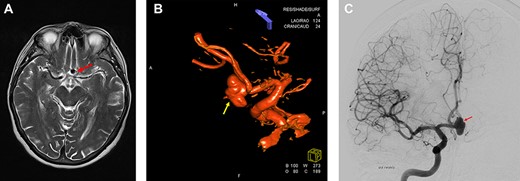

MRI and digitally subtracted angiography showed a large multi-lobulated Acom aneurysm approximately sized 13.0 × 7.5 mm (Fig. 1A–C).

Preoperative neuroimaging. (A) MRI T2-weighted sequence shows an Acom aneurysm without thrombosis. (B, C) Digital subtraction angiography shows a multi-lobulated Acom aneurysm approximately sized 13.0 × 7.5 mm. (B) 3D Digital subtraction.

Endovascular coil occlusion was not considered first-choice treatment because of expected difficulties in properly accessing the aneurysm and in anchoring a stent because of the wide neck and the sharp angle between the aneurysm and the adjacent vessels (anterior cerebral arteries A1 and A2). Consequently, clipping was recommended.